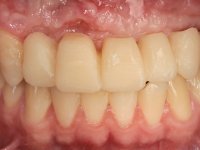

O paciente foi observado conjuntamente e a dúvida que surgiu de imediato foi se seria possível com a regeneração óssea a efectuar poder ser reabilitada naturalmente a zona das papilas interdentárias. Nesse sentido foi feito um enceramento de diagnóstico que contemplaria as duas hipóteses, utilizando ou não a cerâmica gengival. A confecção desse enceramento foi fundamental para expor ao paciente a dificuldade da reabilitação. O wax-up deu origem a um mock-up que foi aprovado pelo paciente e que simultaneamente serviu de guia imagiológica. O caso foi planificado cirurgicamente e realizada uma guia cirúrgica com que foram colocados os implantes. Após 10 semanas foi feita a 1ª impressão para confecção da ponte provisória. Foram criados os primeiros perfis de emergência na gengiva artificial e foi digitalizado o modelo. Por processo de CAD-CAM foi confeccionada uma ponte provisória aparafusada baseada no enceramento de diagnóstico. A ponte trabalhou durante 8 semanas os tecidos moles que foram fielmente copiados numa impressão com técnica de moldeira aberta. Os transferes foram individualizados com resina composta para copiarem fielmente os perfis de emergência criados pela ponte provisória. Confeccionado o modelo de trabalho definitivo, foi realizada uma infra-estrutura em zircónio seguindo a orientação do enceramento de diagnóstico. O assentamento da infra-estrutura foi testado em boca e simultaneamente foi novamente impressionados os tecidos moles com um silicone fluido. Nessa consulta foi feito o levantamento da cor. Os dentes 13 e 23 apresentavam uma saturação anormalmente forte que resolvemos não valorizar, optando por privilegiar a relação com o sector antero-inferior. Foi realizada uma nova gengiva artificial com a impressão que acompanhou a impressão de arrasto com a infra-estrutura. Após a colocação da cerâmica na infra-estrutura foram coladas as meso-estruturas. O trabalho final foi aparafusado lentamente permitindo a adaptação dos tecidos moles.